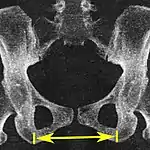

| Interspinous distance | ![]() |

![]() Axial plane |

The line between the closest bone points of the ischial spines | 9.5 to 11.5 cm.[6] | |